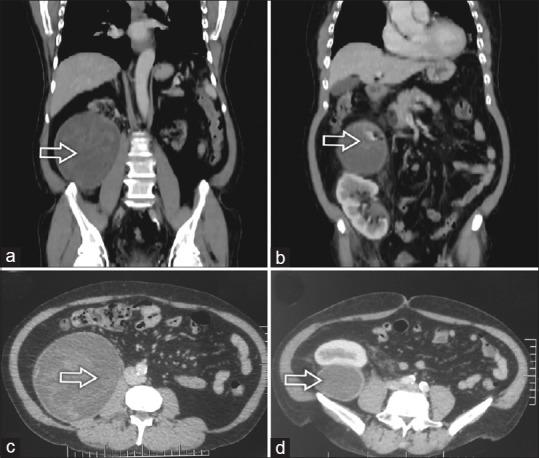

Retroperitoneal gossypiboma mimicking renal tumor in a postrenal transplant patient: A diagnostic challenge.

J Postgrad Med. 2019 Oct-Dec;65(4):247-248. doi: 10.4103/jpgm.JPGM_85_19.